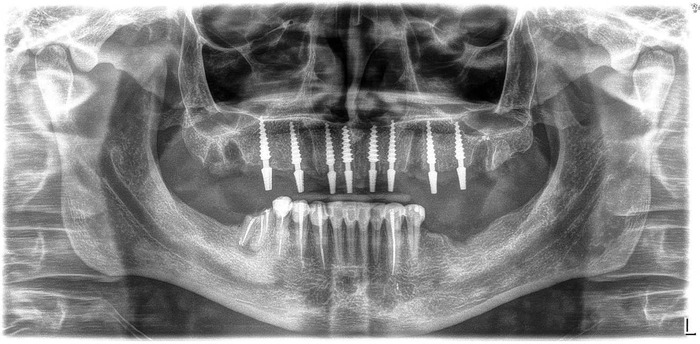

Итак - панорама до:

Как бы уже понятно, что хорошего мало, но к такому я шел примерно лет 20 своей жизни и как-то привык.